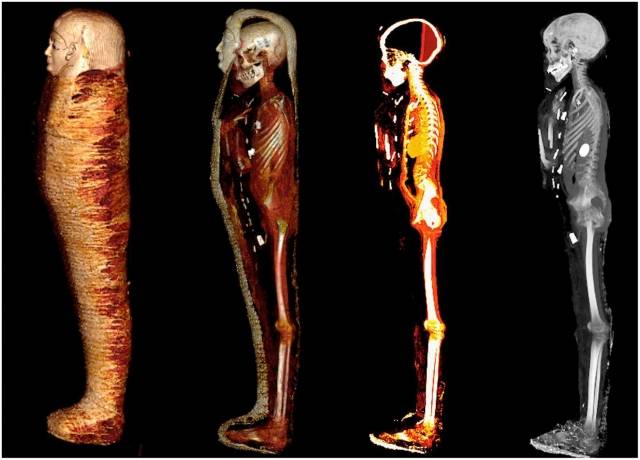

그러나 최근 미라에 직접 접촉하지 않고도 내부를 살펴볼 수 있는 CT 스캔 방식이 도입되며 ‘황금 소년’의 모습이 마침내 세상에 알려지게 됐다.

CT 촬영 결과 이 황금 미라는 총 2개의 관으로 둘러싸인 형태로, 안쪽 나무관에는 금박을 입힌 얼굴 무늬가 새겨졌다.

소년의 나이는 사망 당시 14∼15세, 키는 128㎝ 정도로 추정됐다. 작은 코와 좁은 턱, 계란형 얼굴을 가진 아이였다.